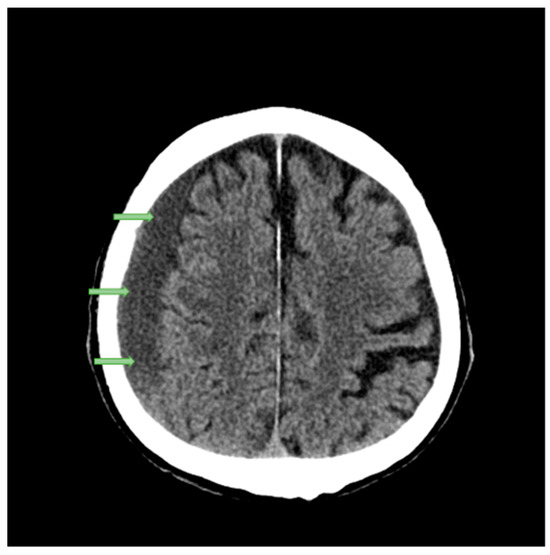

- Tsui, E.Y.K.; Fai Ma, K.; Cheung, Y.K.; Chan, J.H.M.; Yuen, M.K. Rapid Spontaneous Resolution and Redistribution of Acute Subdural Hematoma in a Patient with Chronic Alcoholism: A Case Report. Eur. J. Radiol. 2000, 36, 53–57. [Google Scholar] [CrossRef] [PubMed]

- Kim, H.I.; Oh, Y.J.; Cho, Y.N.; Choi, Y.-C. Subdural Hemorrhage Mimicking Peripheral Neuropathy. J. Korean Neurosurg. Soc. 2014, 56, 166–167. [Google Scholar] [CrossRef] [PubMed]